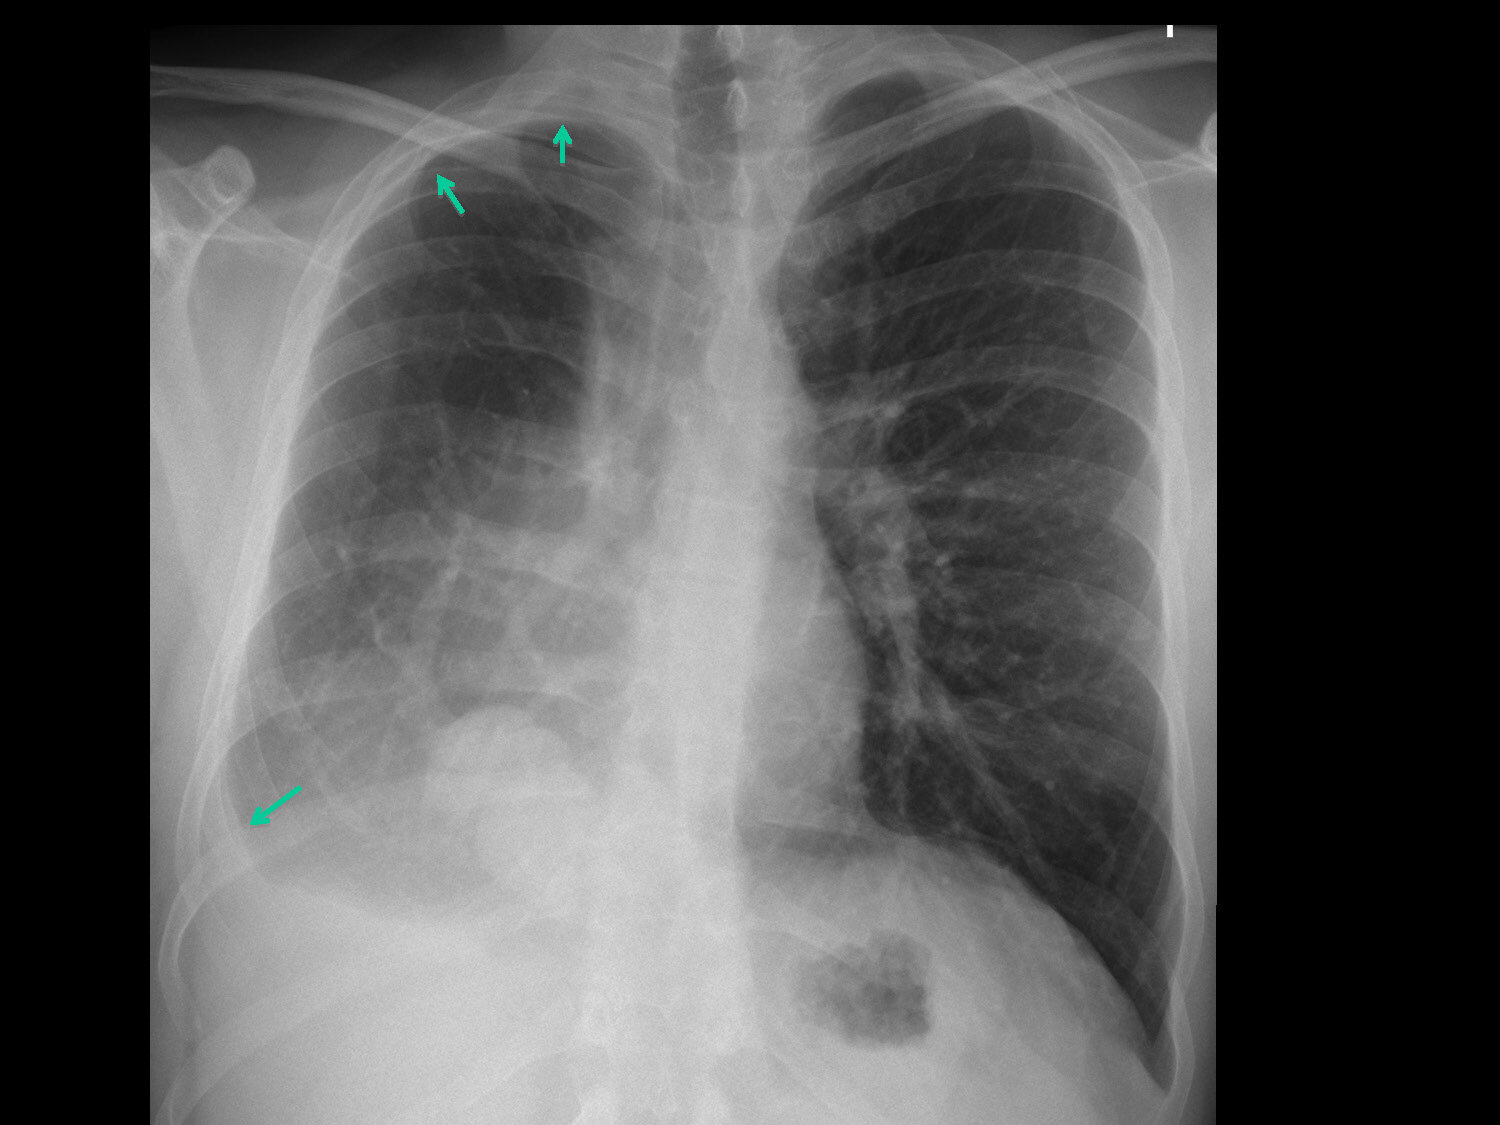

Pleural plaques are best described as small patches of thickening of the parietal pleura, and very rarely the visceral pleura which develop between 20-40 years after exposure.

They are white or pale yellow in appearance and are usually found on the chest wall, diaphragm, and mediastinal pleura.

Varying in number and size, pleural plaques are typically asymptomatic.

Pleural plaques themselves are not pre-malignant and are normally diagnosed via chest x-ray or CT scan.

Diffuse pleural thickening is best described as non circumscribed fibrous thickening of the visceral pleura, with areas of adherence to the parietal pleura and obliteration of the pleural space.

It can spread over an entire lobe or lung, with fibrotic areas involving costophrenic angles, apices, lung bases, and interlobar fissures.

Thickness can range from less than 1 mm up to 1 cm or more.

Diffuse pleural thickening develops 20 to 40 years after initial asbestos exposure and can be caused by all types of asbestos.

The fibrous strands from the thickened pleura extending into the lung parenchyma can be usually be detected on a CT scan.

Pleural plaques often co-exist with diffuse pleural thickening, although pleural plaques on their own are most common.

Symptoms of this asbestos related disease include shortness of breath and chest pain, although most patients are only mildly impaired by the condition.

CT scans can detect early signs of diffuse pleural thickening.

The diagnosis for diffuse pleural thickening describes it as a continuous sheet of pleural thickening more than 5 cm wide, measuring more than 8 cm in craniocaudal extent and more than 3 mm thick.